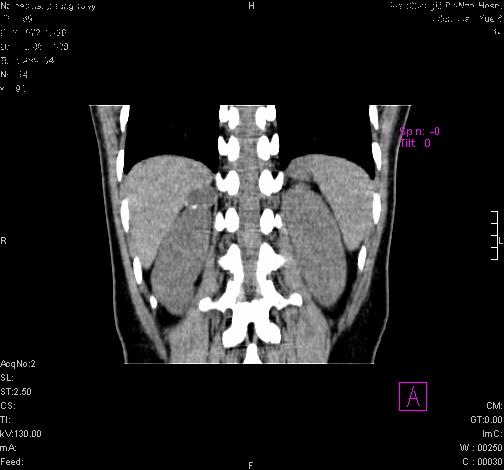

标题: CL0340:【】肾上腺囊肿,比较典型。

患者为年轻女性,查体发现右侧肾上腺囊性占位。无临床体征。

“肾上腺囊肿组织学分为4类:1)内皮细胞性,2)假性囊肿,3)寄生虫性,4)上皮细胞性。其中内皮细胞性最为常见。假性囊肿多为肾上腺内出血后遗留囊腔,囊壁无上皮细胞。寄生虫性多为包虫病引起。上皮性则很少见。”

这么明显的弧形钙化,多考虑包虫病所致的寄生虫性囊肿。

右侧肾上腺囊肿,周围有钙化。